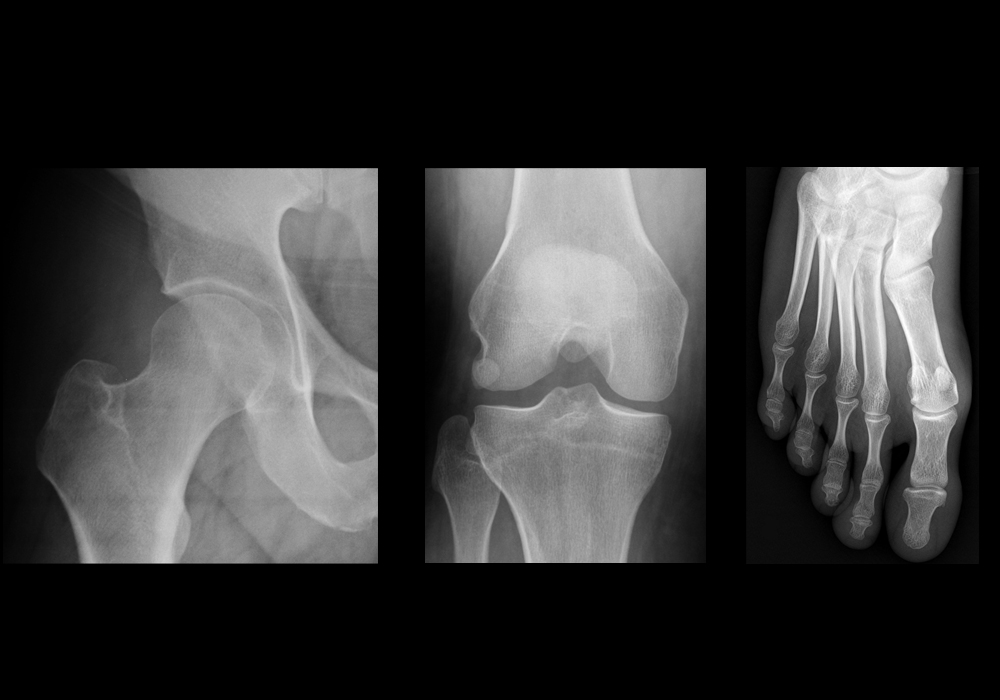

Estudios radiológicos con tecnología digital y mínima exposición a radiación.

Servicio de Rayos X

En Clínica Nuestra Señora de Guadalupe contamos con equipo de Rayos X digital, que nos

permite realizar estudios con alta calidad diagnóstica. Con este sistema, el médico radiólogo

puede llevar a cabo diversos procesos de imagen, como la utilización de zoom, la toma de

mediciones de lesiones, medidas cardiotorácicas, cálculos de ángulos para estudios de

ortopedia, inversión de imágenes, aplicación de filtros para mejorar la toma radiográfica o para

disipar dudas en cuanto a la etiología de las lesiones que pudiesen observarse.